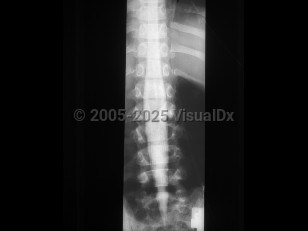

Diastematomyelia in Adult

Diastematomyelia, split-cord malformation (SCM), is a rare congenital abnormality in which there is partial or complete cleft in the spinal cord by a sagittal osseous or fibrous septum. It is seen predominantly in females, most often affecting the lower thoracic or upper lumbar segments. Clinically, diastematomyelia often presents as tethered cord syndrome (back pain, abnormal gait, spasticity, bowel / bladder incontinence) in children or young adults, although symptom onset may occur at any age. Patients may have a midline cutaneous abnormality such as a hairy patch or dimple over the affected area. There are two classifications: